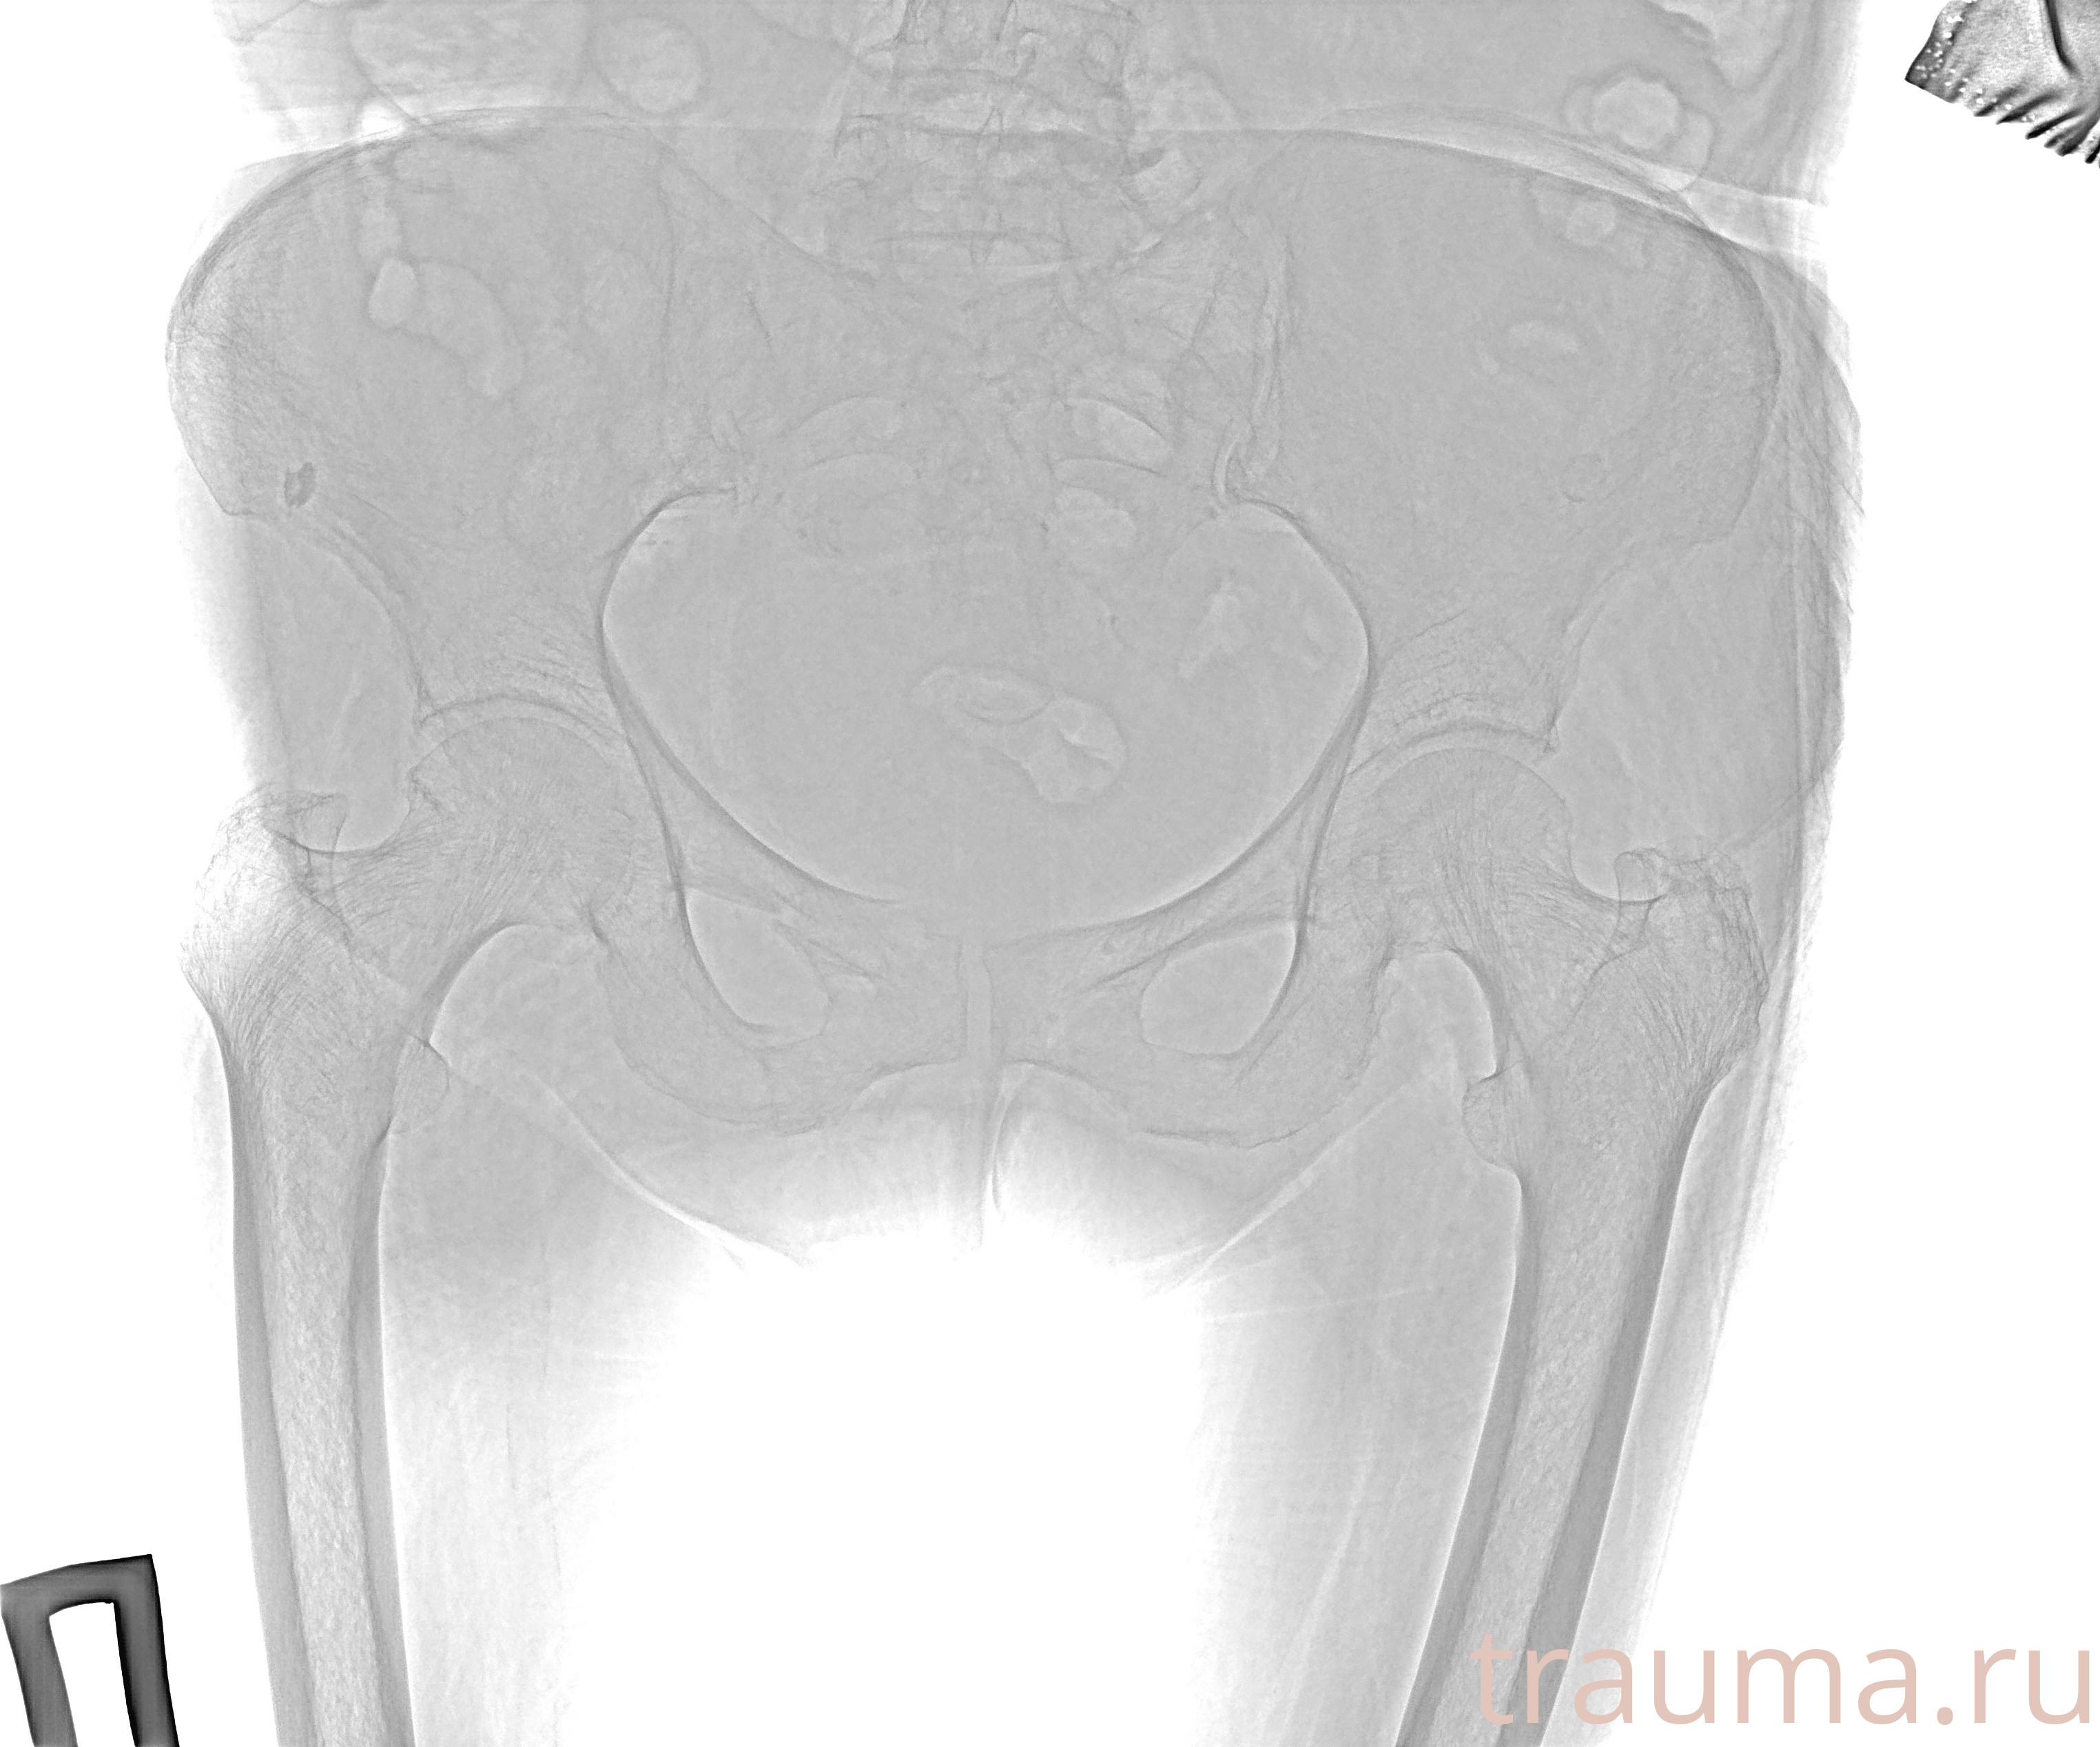

Первая помощь при переломе шейки бедра

Рентген на дому: по вашему адресу приезжает врач-рентгенолог, травматолог-ортопед с мобильным рентгеновским аппаратом, проводит диагностику травмы или заболевания, делает необходимые рентгенограммы, дает рекомендации по дальнейшему лечению. Получить качественные снимки в домашних условиях возможно благодаря уникальной методике, разработанной МосРентген Центром для института  Склифосовского